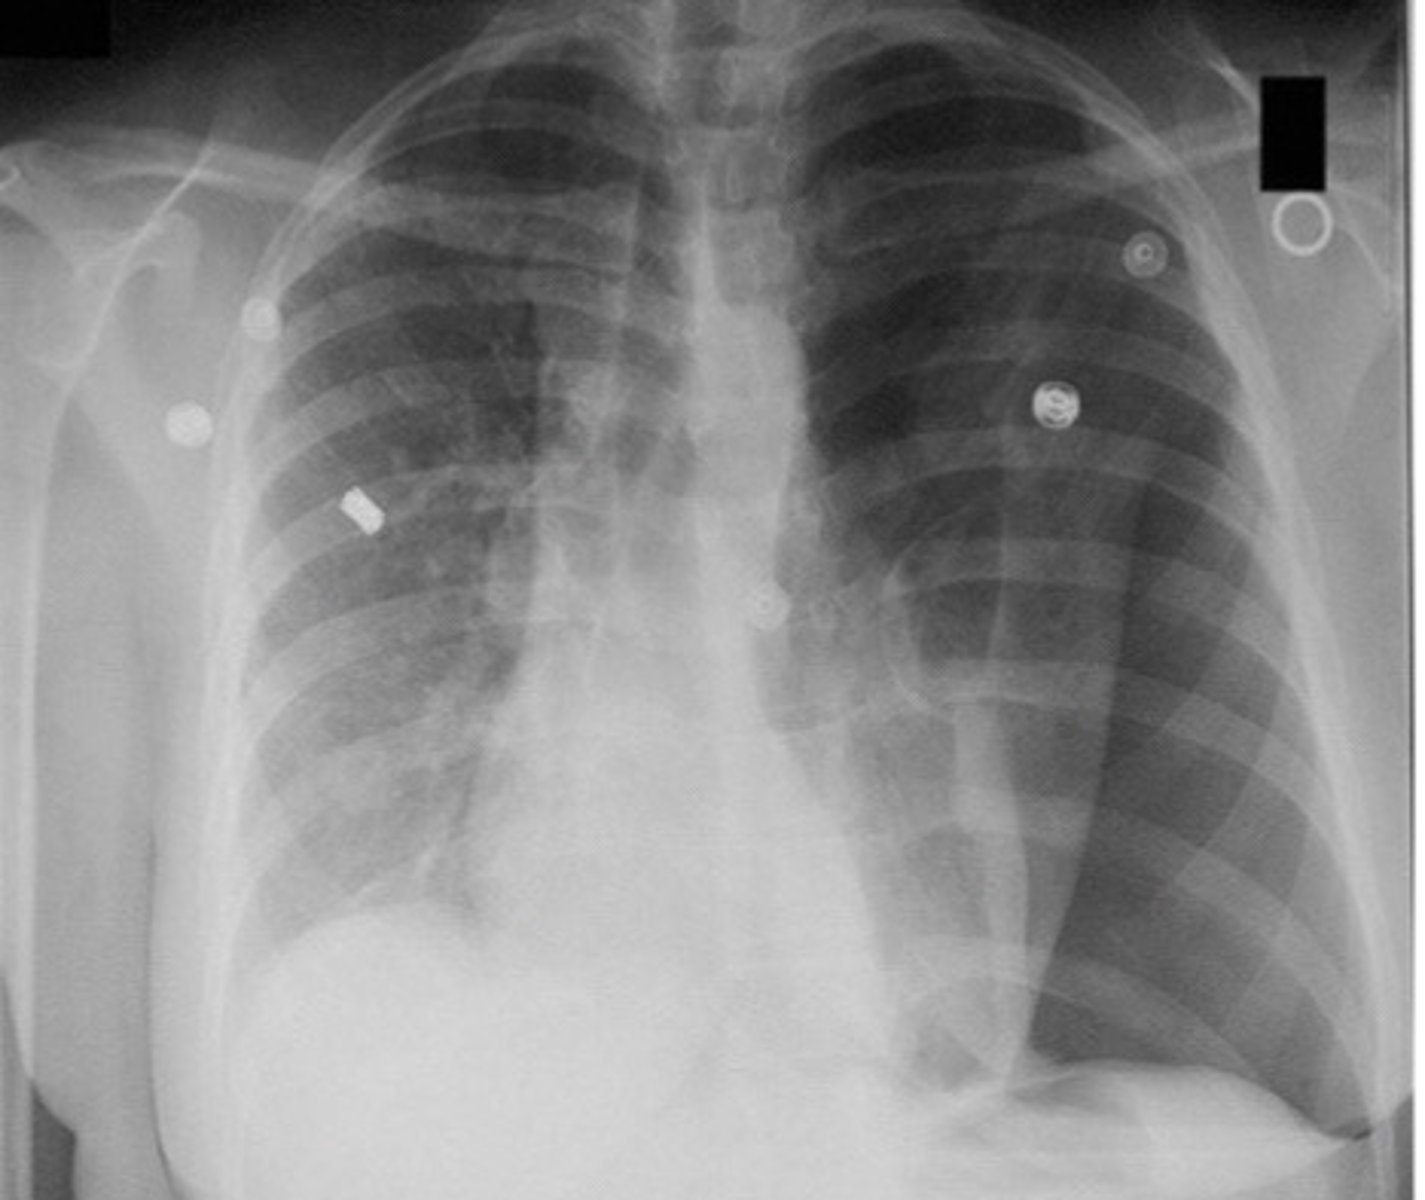

Types of pneumothorax

Iatrogenic: secondary to procedure

Primary spontaneous: healthy pts, no trauma

Secondary spontaneous: known lung dx

92

New cards

GS diagnostic testing for pneumothorax

Upright PA CXR

96

Visualization of visceral pleural line on CXR is indicative of

Pneumothorax

<p>Pneumothorax</p>